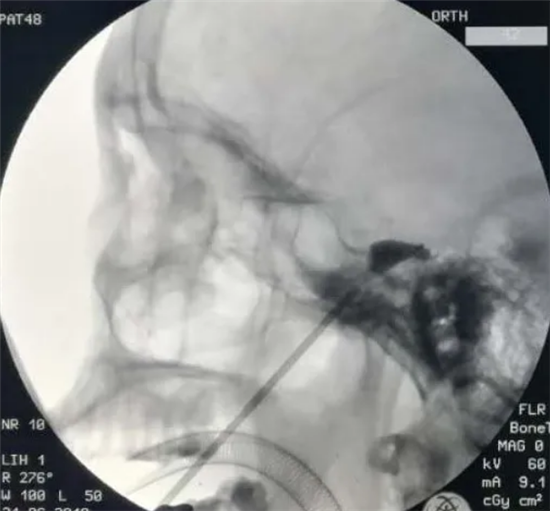

金森病是常见的老年退行性疾病,给老人的生活带来极大的影响,在药物治疗效果不佳的情况下,脑深部电极植入术能够极大提高患者的……

三叉神经痛是发生于颜面部三叉神经分布区内的一种突发突止的、反复发作的剧烈疼痛。正常的洗脸、刷牙、进食常可诱发疼痛发作,因……